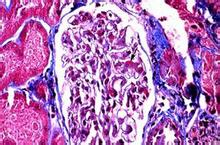

腎小體血管球(glomerulus

):血管球(一團蟠曲的動脈性毛細血管球)是位於腎小囊內的一團蟋曲的毛細血管,由進球小動脈從血管極處入腎小囊內,先分成4—5支,每支再支形成許多相互吻合的毛細血管袢,繼而再匯合成一條出球小動脈,從血管極處離開腎小體。電鏡下,血管球毛細血管為有孔型,孔上大多無隔膜,有利於濾過功能。每個血管袢之間在有血管系膜支持,毛細血管繼而又

匯成一條出球微動脈,從血管極處離開腎小囊。因此,血管球是一種動脈性毛細血管網。由於進球微動脈管徑較出球微動脈粗,故血管球內的血壓較一般毛細血管的高,當血液流經血管球時大量水和小分子物質易於濾出管壁而入腎小囊內。電鏡下,血管球毛細血管為有孔型。孔徑50~100nm,有利於濾過功能。在內皮細胞的腔面復有一層帶負電荷的富含唾液酸的糖蛋白(細胞衣),對血液中的物質有選擇性通透作用。內皮外面大都有基膜,但在面向血管系膜一側的內皮則無基膜,此處的內皮細胞與系膜直接接觸。

腎單位腎小球毛細血管的結構也較其它部位的毛細血管複雜,由內皮細胞、基底膜和上皮細胞組成,稱為濾過膜。